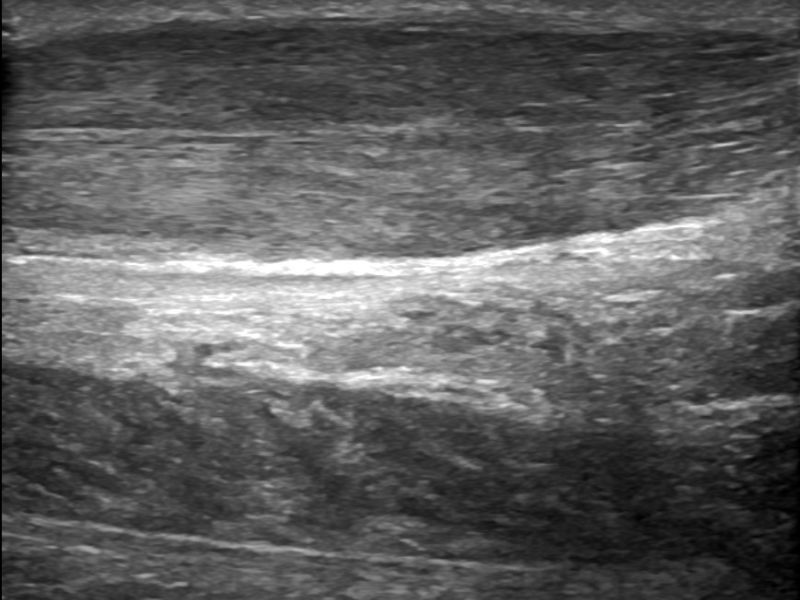

Foot Tendons

Foot Ultrasound allows the diagnosis of tendonitis, tenosynovitis, and rupture in the following tendons:

- Achilles Tendon

- Peroneal Tendons

- Flexor Tendons

- Extensor Tendons